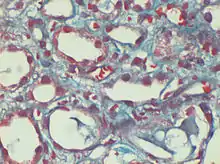

Dilated peri-tubular capillaries filled with sickled RBCs, original Gomori's trichrome stain, × 400.[1]